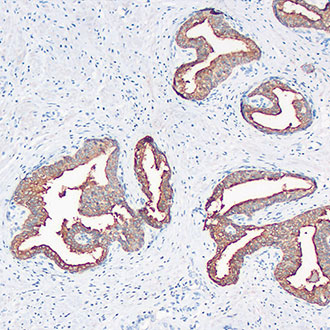

CK7

CK7 -